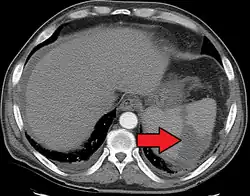

Splenic infarction is a condition in which blood flow supply to the spleen is compromised,[1] leading to partial or complete infarction (tissue death due to oxygen shortage) in the organ.[2] Splenic infarction occurs when the splenic artery or one of its branches are occluded, for example by a blood clot.[3]

An abdominal CT scan is the most commonly used modality to confirm the diagnosis,[3] although abdominal ultrasound can also contribute.[5][6][7]